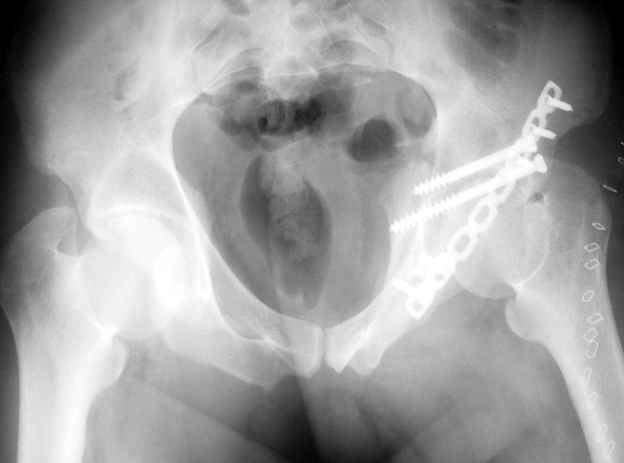

шейку (благо перелом шейки 2 типа -относительно стабильный) затем фрагмент крыла подвздошной кости Lag screw, далее пластина на заднюю колонну и винты в переднюю колонну.(с размерами и направлением винтов ошибка вышла:-((, но интраоперационно у меня была полная уверенность , что винты *ушли* в лонную кость).

Еще раз спасибо за комментарии и готовность помочь с имплантами. Постоп картинки в приложении,

С наилучшими пожеланиями,

Евгений Чекашкин